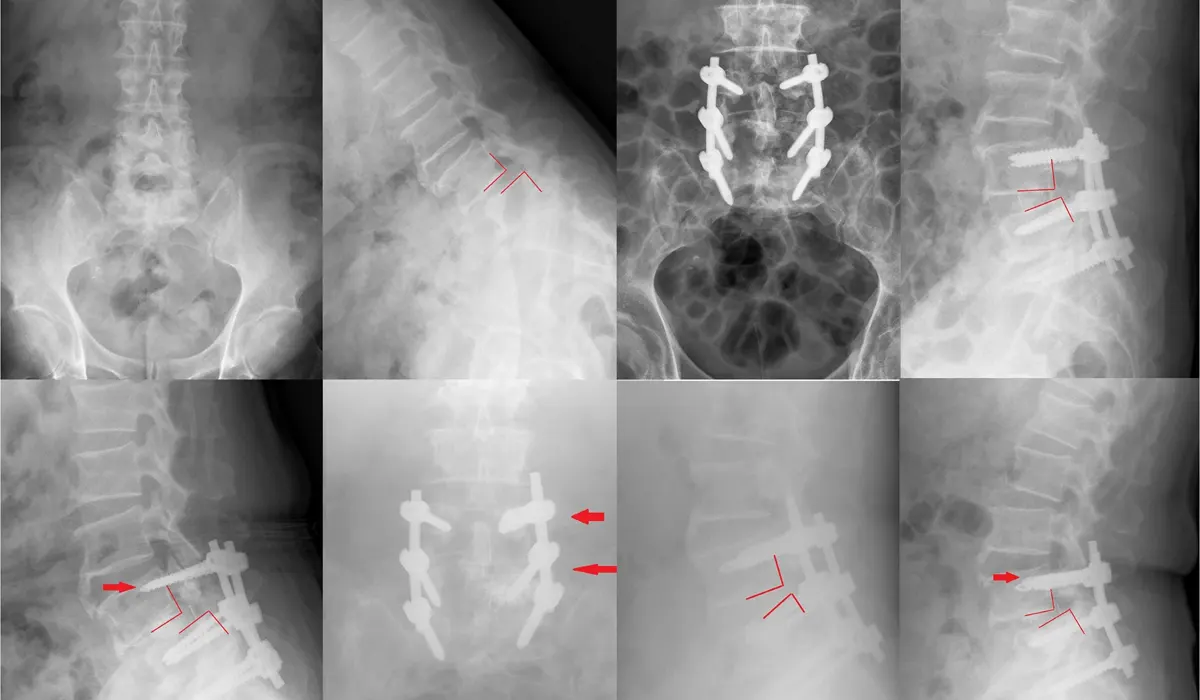

The use of Cannulated Pedicle Screw to treat AIS decreases perforation and complication rates. Although it did not significantly lower the medial perforation rate, it dramatically reduced the lateral perforation rate. The use of cannulated screws enables intraoperative confirmation of placement accuracy. Cannulated Pedicle Screws use to treat AIS is safer and more efficient.

Pedicle Screw are used in a spinal fusion to add extra support and strength to the fusion while it heals. The screws themselves do not fixate the spinal segment, but act as firm anchor points that can then be connected with a rod.